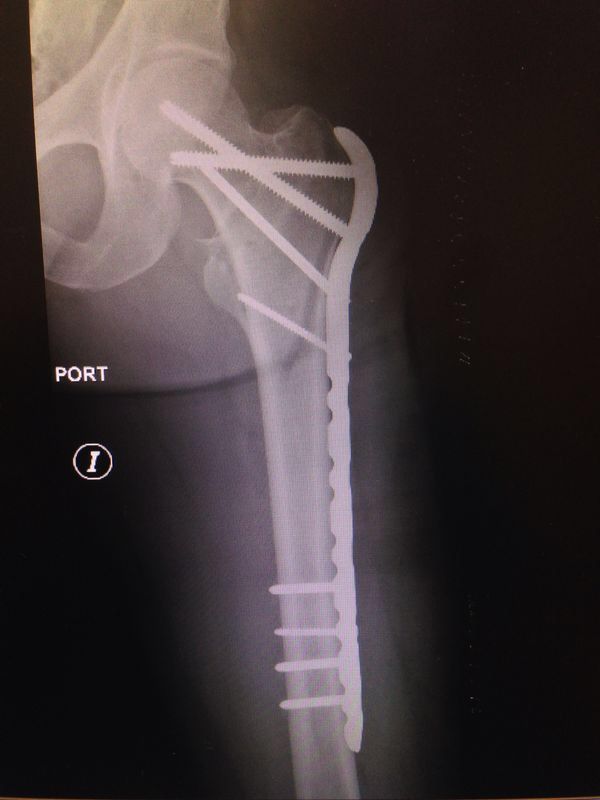

• Cirugía cadera

• Prótesis de cadera

Artroplastia de la cadera con prótesis total

El desgaste articular de la cadera, se traduce en dolor para el paciente afectando su calidad de vida. Existe un procedimiento quirúrgico mediante el cual, se realiza una sustitución de la articulación de la cadera por un implante que realiza la función de la misma. De esta manera se quita el dolor por completo del paciente restituyendo la anatomía normal, y mejorando de manera significativa la calidad de vida del paciente.